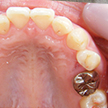

6. 施術前上顎観

上顎左右の8番(移植歯としての利用は断念)、および左上4番の抜歯した後の上顎写真です。これを見て思うのは、1歯レベルではとても良質の歯をしているのに、6番(6歳臼歯)が失活(神経を取った)又はかぶせ物がなされていることから、小学校から高校くらいまでの間は混合歯列期(乳歯と永久歯が共存している時期)や最初に萌出する6番の時期に、歯科的なアプローチが結果的に不十分だったことです。